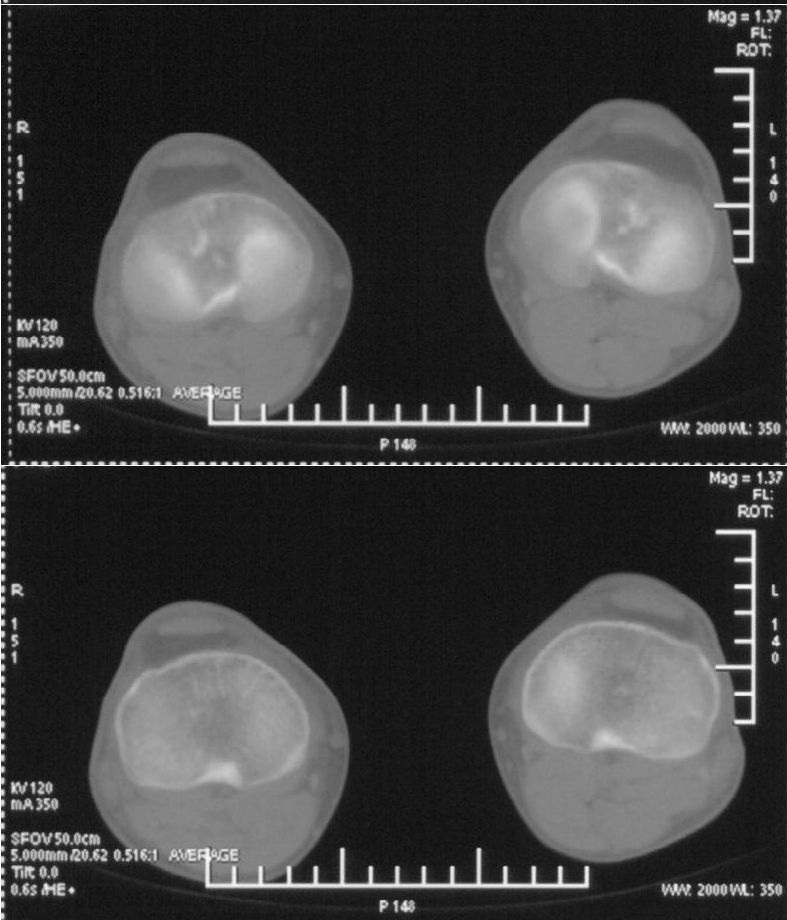

男,42岁。4个月前钢筋钝伤右侧小腿部,当时因无明显外伤,未引起重视。一周后因受伤腿部疼痛,发现肿胀,随后到当地医院进行检查(2008年4月16日)。因未发现骨质异常未引起重视,仅仅进行口服抗生素治疗处理。经过一段时间治疗但未见明显治疗效果在5月29日又进行x线检查,发现有胫骨密度上段密度增高,又进行抗炎治疗,仍未见效果。又在7月3日进行x线检查,仍然报告有胫骨上端密度增高,并建议ct检查。以下是相关检查结果:

髓腔密度呈絮状增高,胫骨上端内侧可见层状骨膜反应,考虑骨髓炎.

髓腔密度呈絮状增高,胫骨上端内侧可见层状骨膜反应,肌间隙模糊,考虑骨髓炎.

破坏、增生、骨膜反应,考虑骨髓炎

这个ct是ge high speeds 64排。